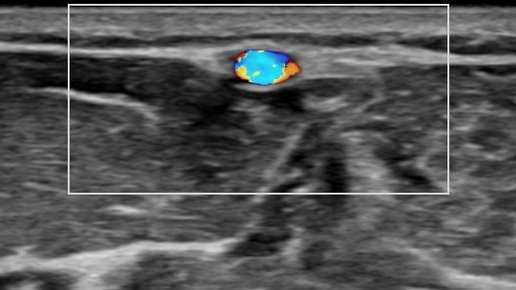

Вариант строения артерий верхней конечности (УЗИ)